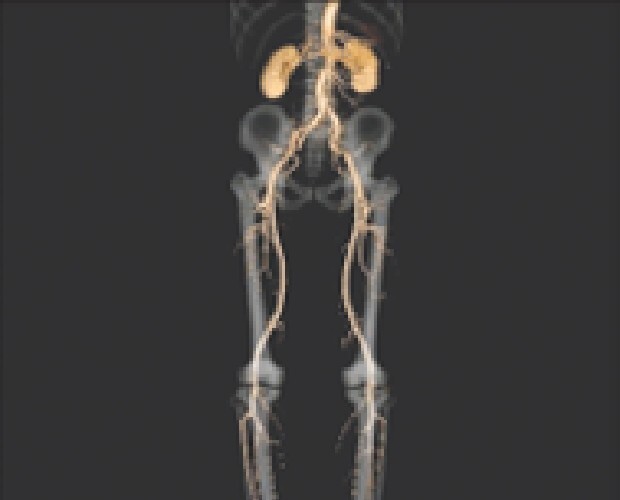

マルチスライスCTスキャナは寝台に横になるだけで頭部・胸部・腹部など体内を断層(輪切り)で撮影できる検査です。

従来装置(64列)に比べて高速、高精度の撮影が可能なだけでなく、患者様の体型に合わせて線量を可変できるため適切なX線量で検査できます。

診断や治療のために骨や血管の3D(立体的な三次元画像)を作成することもできます。